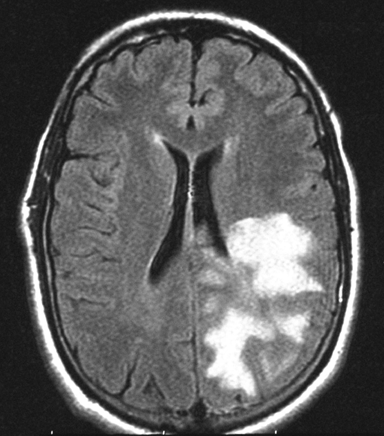

The FLAIR sequences (Panel A) demonstrate an extensive abnormality with increased intensity signal and irregular borders that involves the left occipital, parietal and dorsal frontal lobes. Although the lesion is quite extensive the mass effect is minimal. On the post contrast T1-weighted sequences (Panel B) there is enhancement only in the anterior border of the lesion. The limited mass effect along with the “crescent” rim enhancement are suggestive of  demyelinating process, likely tumefactive multiple sclerosis.